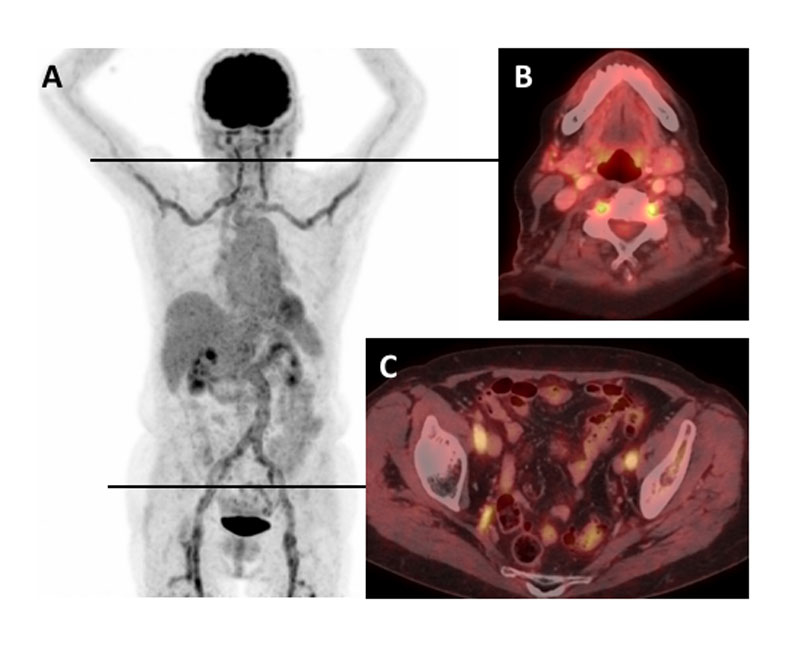

Increased FDG uptake in the vessel wall is the hall-mark of vasculitis in PET (figs 3 and 4 ). Uptake can be graded visually, by semiquantitative analysis, or using standardised uptake values (SUVs) [29–31]. In general, visual vascular uptake higher than tracer uptake in the liver is considered suspicious for large-vessel vasculitis [30]. Furthermore, a smooth linear or long segmental pattern of FDG uptake in the aorta and its main branches is a characteristic pattern of GCA [31–33]. Differentiation between vasculitis and atherosclerosis remains a challenge with PET/CT [31, 32]. The discrimination is mostly based on qualitative assessments; hence it is strongly dependent on the experience of the reader. Vasculitic vessel wall changes are more homogeneous, linear and without calcification (fig. 4A). In contrast, arteriosclerotic lesions are marked by calcifications, a patchy distribution, or minor vessel wall pathologies at predilection sites of arteriosclerosis. As a result of the high arteriosclerotic load in lower limbs arteries, enhanced tracer uptake in this area has lower specificity than in the aortic branches [34].

Figure 3 Increased fluorodeoxyglucose (FDG) uptake in the large arteries of a patient with untreated giant cell arteritis. (A) Maximum intensity projection gives an overview including comparison to the liver FDG uptake. Axial positron emission tomography / computed tomography fusion images showing (B) FDG uptake in the vertebral arteries, and (C) FDG uptake in external and internal iliac arteries.